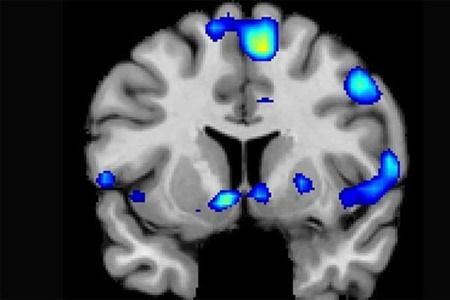

تشخیص محل HIV در مغز با اسکن MRI

به گفته محققان، به رغم درمان دارویی موثر ممکن است ویروس HIV در مغز باقی مانده و منجر به مشکلات شناختی شود.

محققان دریافتند پیگیری تغییرات ماده سفید مغز با استفاده از اسکن MRI می‌تواند به شناسایی محل این ویروس مرگبار کمک کند. به گفته محققان، ویروس HIV در مغز حدود ۱۰ تا ۱۵ درصد بیماران پخش می‌شود.

یافته‌ها نشان داد بیمارانی که در مغزشان علائم قطعی تغییر در ماده سفید وجود داشت ۱۰ برابر بیشتر از افراد دارای ظاهر عادی ماده سفید دارای HIV در مغزشان بودند.

این تغییرات در مغز موسوم به «اختلالات سیگنال دهی ماده سفید» با مشکلات شناختی مرتبط بوده و بواسطه التهاب در مغز ناشی از عفونت HIV ایجاد می‌شوند.

به گفته محققان دانشگاه کالج لندن، روند درمان HIV بسیار طولانی است اما بیمارانی که HIVشان بواسطه دارو متوقف شده است هنوز هم به دلیل التهاب مرتبط با HIV دارای مشکلات شناختی هستند.

به گفته تیم تحقق، «مطالعه جدید ما نشان می‌دهد اسکن MRI می‌تواند به شناسایی افراد پرخطر برای ازمایشات بعدی کمک کند و با شناسایی این افراد درمان دیگری برای آنها تجویز شود.»